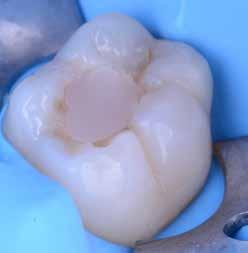

Az 53 éves hölgy páciens jobb felső 6-os fogában látható amalgámtömés cseréje volt a cél. A tömés mellett secunder caries és az amalgám következtében létrejött mesialis zárólécen áthaladó repedés, továbbá mesialis caries figyelhető meg (1. ábra). El kellett kerülni, hogy a tömés kifúrásakor az amalgámtörmelék a páciens szájába kerüljön, esetleg ebből valamennyit lenyeljen, a kezelés első lépésként kofferdám izoláció került fel a jobb felső kvadránsba (2. ábra). A kapocs a 1.7 fogra került, ezzel kényelmesen helyet teremtett a későbbiekben felkerülő matricarendszernek. Az egyszerre több fog izolálása lehetővé teszi, hogy a szomszédos fogak referenciául szolgáljanak a restauráció felépítése közben.

A régi amalgámtömés eltávolítását követően caries indikátor segítette a carieses laesio megfelelő kitisztítását a pulpa expozíciója nélkül. Ezután kerülhetett sor az ideális üregdesign kialakítására, továbbá a zománcszélek finírozására (3. ábra) Az approximális box megnyitása során az alátámasztatlan zománcprizmák eltávolításra kerültek, ezzel is csökkentve a secunder caries képződés veszélyét. Az így kialakuló forma elősegíti a matrica megfelelő adaptációját, végül pedig az approximális box határainak a hozzáférhetőségét, így finírozás során ez jobban kontrollálható és polírozható.

A Palodent V3 matricarendszer felhelyezését követően a zománc 10 másodperces szelektív savazása, majd lemosása és leszárítása után történt a kavítás bondozása Prime & Bond Universallal.

Kulcslépés: a II. osztályú üreget a matricarendszer segítségével I. osztályúvá lehetett átalakítani.

A pontosabb széli záródás érdekében célszerű a matrica illesztési határába némi folyékony kompozitot felvinni (NeoSpectra ST flow A2), majd megvilágítás nélkül a zárólécet paszta kompozittal (NeoSpectra STHV A2) felépíteni, miközben a kifolyó fölösleges folyékony kompozit eltávolításra kerülhet. Így ki lehetett használni és kombinálni a két különböző konzisztencia előnyeit.

A polimerizációt követően kerülhet sor a matricafeszítő gyűrű, valamint a matrica eltávolítására. A Palodent V3 fülekkel ellátott matrica kialakításának és a speciális PinTweezers csipesznek hála, a feszes kontaktpont ellenére a matrica könnyedén eltávolítható. Az éket viszont a kezelés végéig

célszerű bennhagyni, elkerülve egy esetleges nemkívánatos vérzést (4. ábra)

A matrica és gyűrű nélkül az approximális fal magassága, valamint a szomszédos fogakhoz viszonyítható dimenziók jobban megállapíthatóak. A jobb térlátás és a nagyobb mozgástér precízebb eredményhez vezet, csökkentve ezzel az utólagos finírozás mértékét, továbbá a részletgazdagon kialakított anatómiai struktúrák torzulásának az esélyét. Az üreg mélyebb részei SDR Plus A3-mal kerültek feltöltésre, majd NeoSpectra STLV A3-mal kiegészítve vált teljessé a dentin pótlása (5. ábra), ezzel létre lehetett hozni egy homorú formájú kromatikusabb alapot.

Ezt követően csücsökről csücsökre haladva a felső hatosokra jellemző anatómiai struktúrák, megfelelő orientációval bíró csücsöklejtők és elsődleges barázdák Neo Spectra

HV A2 anyagból kerültek kialakításra (6. ábra). Apró „kompozit-hurkákkal” kiegészítve létrehozható a csücskökön belüli tagoltság, ezzel kialakítva a másodlagos barázdarendszert és egy sokkal kidolgozottabb anatómiai struktúrát (7. ábra). A fogorvos esetleges „művészi hajlamát” is figyelembe véve, a természethű megjelenés barázdafestéssel (Micerium - Stain Brown 2) még tökéletesebb lehet (8. ábra). Ezzel a korábban részletgazdagon kialakított ba-

rázdarendszer kiemelhető, és optikailag fokozható a gödröcskék mélysége is.

A restauráció megfelelő polimerizációja után célszerű a kofferdám nyújtotta retrakciót kihasználni, és a restauráció széli záródásában levő esetleges kompozitfölösleg elfinírozását jobb rálátás mellett elvégezni (9. ábra). Ebben nagy segítségünkre lehet az Enhance rendszer, mely a kompozitot nagyon szépen elsimítja, de a természetes fogszövetet nem bántja.

A matricázott terület széli záródásának a kidolgozásában az EVA polírozó (10. ábra) lehet a segítségünkre, amellyel a gingiva sérülése megelőzhető, és a kialakított feszes kontaktpont sem kerül redukcióra (11-12. ábra)

A kofferdam eltávolítását követően kerülhetett sor az occlusio beállítására csücsöklejtők domborúságának a redukciója révén (13. ábra). A harapás gyémántfúrókkal történő beállítása után a polírozás Enhance rendszerrel történt, melynek végső lépéseként a PrismaGloss használatával (14. ábra) nyerhette el a restauráció a végső fényességét (15. ábra)

A ma rendelkezésre álló modern eszközöknek és anyagoknak hála II. osztályú üregek direkt módon kiszámíthatóan restaurálhatóak. A matricarendszernek köszönhetően helyreállítható a feszes kontaktpont, a „kaméleon effektussal” bíró kompozit pedig a tömés integrációjáért felel. A megfelelő adhézió, a precízen kidolgozott széli záródás és a plakkréteg megtapadását nehezítő polírozott felszín a kezelés hosszú távú sikerének a garanciája. Mindezek együtt egy hosszú távon tartós, funkcionális és esztétikai rehabilitálást tesznek lehetővé.